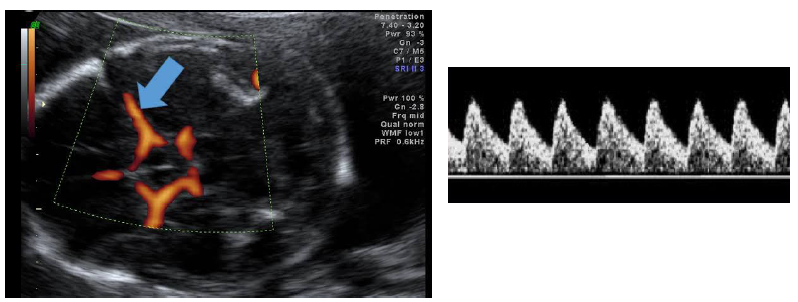

Com base nas imagens, assinale a artéria que está sendo estudada e a conduta esperada.

Umbilical – manter pré-natal habitual.

Cerebral média – manter pré-natal habitual.

Umbilical – encaminhar à maternidade/médico assistente.

Cerebral média – encaminhar à maternidade/médico assistente.